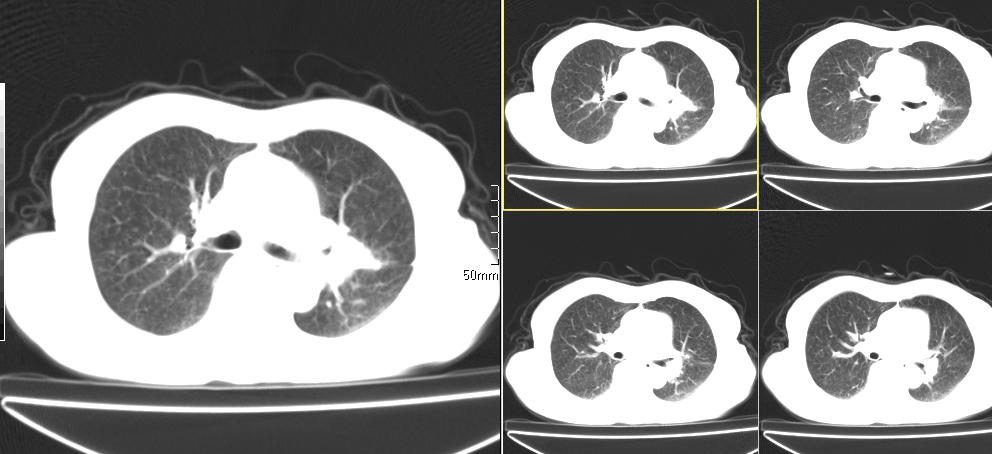

标题: CT26857:女,60岁,胃部不适前来就诊,不咳嗽,乏力,胸椎 [打印本页]

1、胸椎有骨质破坏伴周软组织,考虑胸椎转移。2、考虑左肺上叶尖后段支气管开口区周围型肺癌可能。

1、胸椎有骨质破坏伴周软组织,考虑胸椎转移。2、考虑左肺中央型肺癌可能。

支持中央型肺癌,胸椎转移。

1)考虑左肺中央型肺癌。2)胸椎转移瘤不排除;建议行mri检查。